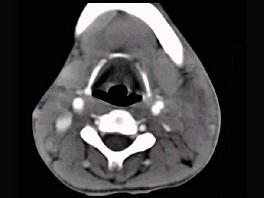

问题 男性,67岁,颈部出现疼痛性肿块半年余,CT扫描如图所示,最可能的诊断是 ( )

选项 A、淋巴瘤 B、血管瘤 C、囊肿 D、淋巴结核 E、神经鞘瘤

答案 A